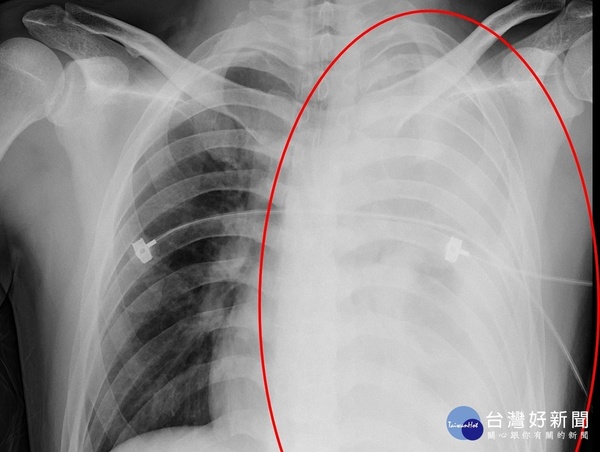

衛福部臺北醫院27歲陳先生騎機車出車禍,沒有明顯外傷但感覺左肩疼痛,送醫經初步X光及胸腔電腦斷層顯示肋骨骨折,合併輕微氣胸且有微量的胸腔積液。由於意識清楚、精神不錯且血壓、心跳正常,陳先生原本想直接回家,但醫師建議住院觀察一段時間。沒想到三個小時後,陳先生突然昏迷,立即安排血管攝影式的電腦斷層顯影檢查,及時發現左鎖骨下血管斷裂的部位,透過心導管定位及胸腔鏡手術迅速止血之後,救回一命。

胸腔外科林振嵩醫師表示,此案例比較特殊,並非是肋骨斷裂處出血,而是肺尖與鎖骨下動脈有新生血管斷裂出血,推斷是在出車禍瞬間發生氣胸,後續的肺塌陷扯斷此血管。當胸部受到撞擊時,雖然沒有外傷,但間接傷害可能造成氣胸,每十個氣胸病人可能其中一人會併發血胸,若嚴重則會造成肺部塌陷而休克致命,必須緊急進行開胸手術或是用胸腔鏡進行止血。若能及時處理,大多數的血胸病人都能恢復,且不會留下後遺症。透過心臟外科與胸腔外科團隊的合作,提供最快速、最適切的醫療,讓病人沒有後遺症順利恢復健康,是創傷團隊最大的肯定。